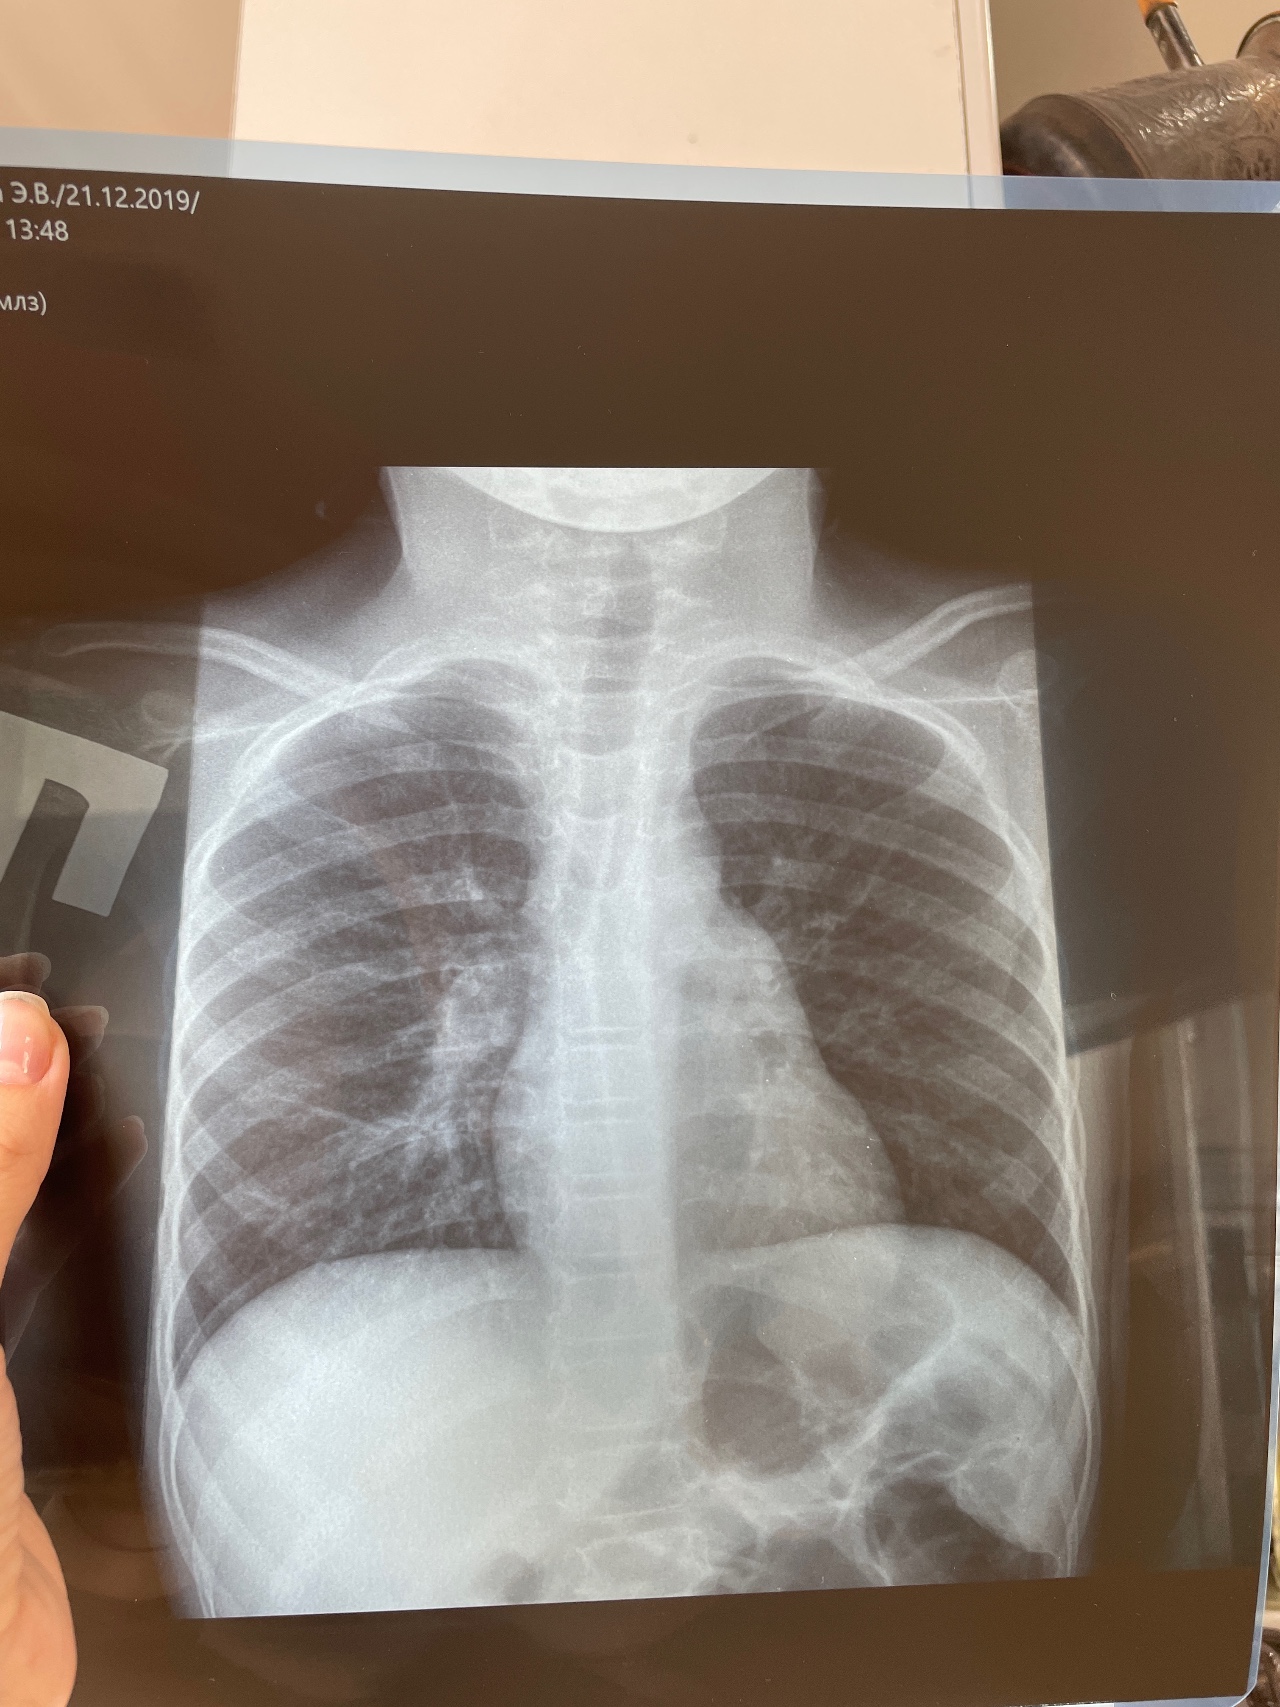

Что видите на ренгене, есть ли пневмония?

Здравствуйте, рентген сделали на третий день кашля, при прослушивание было подозрение на пневмонию. Была температура 4 дня, в среднем 38. Кровь спокойная, ни вирусная, ни бактериальная. Видите ли вы тут пневмонию?